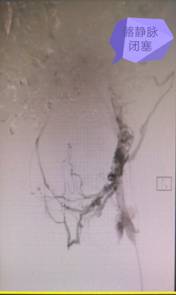

患者老洪“老烂腿”多年,反复左下肢皮肤瘙痒、溃烂,经久不愈,严重影响生活质量。他曾经到外地大医院及专科医院治疗,也曾经手术,但是,都没有办法,“老烂腿”给他的健康和正常生活带来了很大的影响。后来慕名来到瑞医。经瑞医介入科施昌盛医师检查,诊断为左髂静脉压迫综合征,由于髂静脉闭塞,左下肢静脉回流不畅导致静脉淤血而引起下肢反复溃疡。施医师认真与老洪进行沟通,让他放下思想包袱,树立了信心。6月30日,施医师团队给予了介入治疗—左髂静脉支架置入开通闭塞的血管,不用开刀,只需要一个2mm的穿刺点,送入导丝,开通血管,术后3天,患者下肢溃烂明显好转,术后10天,下肢溃烂愈合。

“老烂腿”形成原因主要是下肢血管性因素,包括下肢静脉曲张、下肢静脉血栓形成、髂静脉压迫综合征、下肢动脉硬化闭塞症、糖尿病足、脉管炎。而这些都是可以通过介入微创治疗取得很好的疗效。这几年,类似老洪的“老烂腿”已经治愈好多人了。